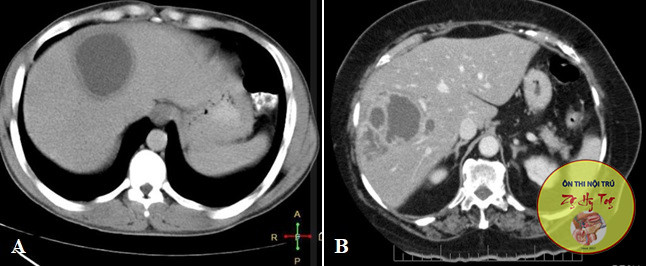

Ca lâm sàng thực tế, vận dụng lý thuyết bệnh học